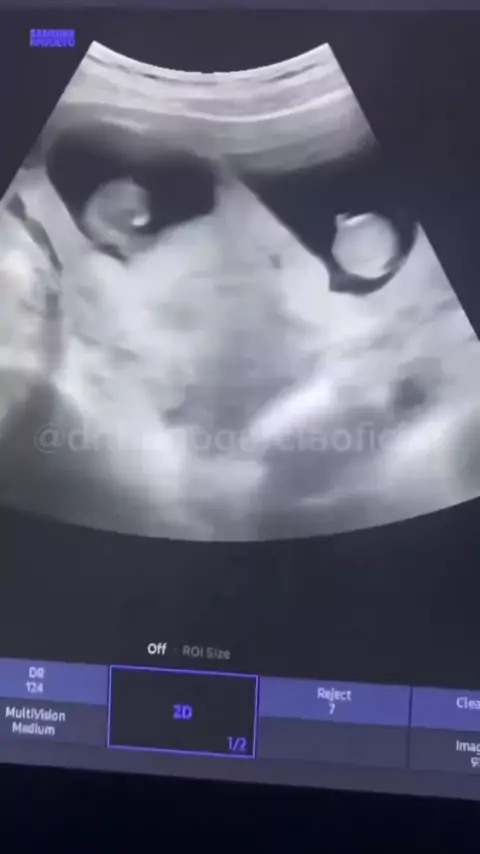

Mãe descobri que está grávida de trigêmeos e pai desmaia ☺️ #